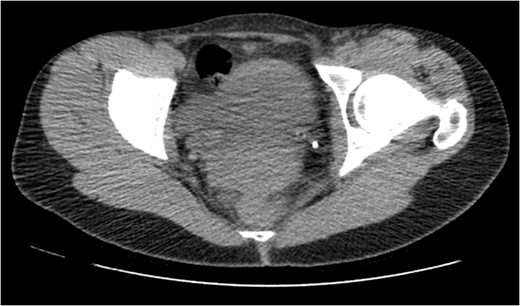

CT IVU- confirmed extravasation of contrast medium around the left kidney and ureter, the rupture being at the level of the PUJ.